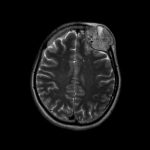

707

'25年12月

80代

髄膜腫

頭蓋内腫瘍摘出術

No.’25_109 手術前1

No.’25_109 手術前2

No.’25_109 摘出 前

No.’25_109  摘出 中

No.’25_109 摘出 後